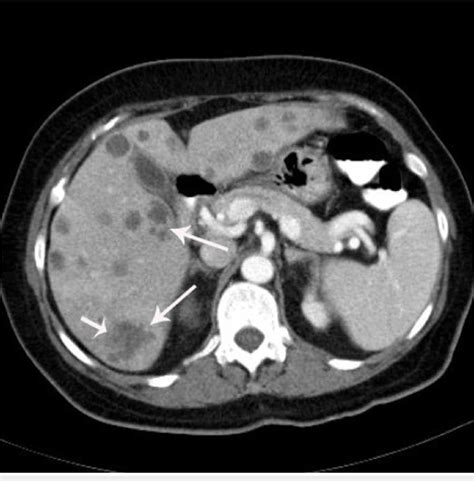

• Imaging Studies: Imaging techniques such as ultrasound, computed tomography (CT) scan, and magnetic resonance imaging (MRI) can visualize the abscess and determine its size and location.